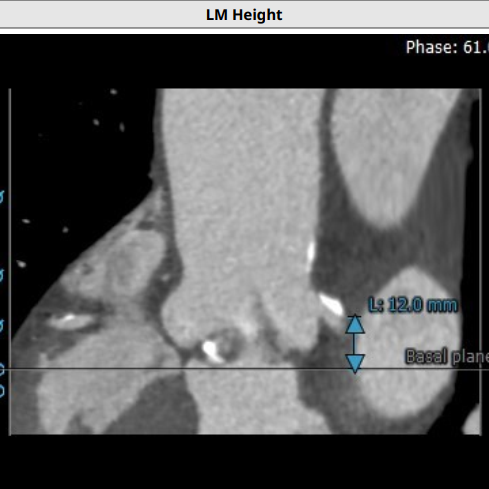

超声心动图显示,主动脉最大流速482cm/s,最大压差93mmHg,平均压差50mmHg,LVEF65%。CT显示主动脉瓣为TYPE2型二叶瓣,严重钙化,右无、左无可见粘连伴钙化,瓣环平面可见钙化,钙化延伸至流出道及二尖瓣前叶根部,左冠高度约12mm,瓣叶长度14.9mm,存在一定左冠风险,法式窦平均直径33.7mm,STJ高度约21.8mm、直径约30.2mm。